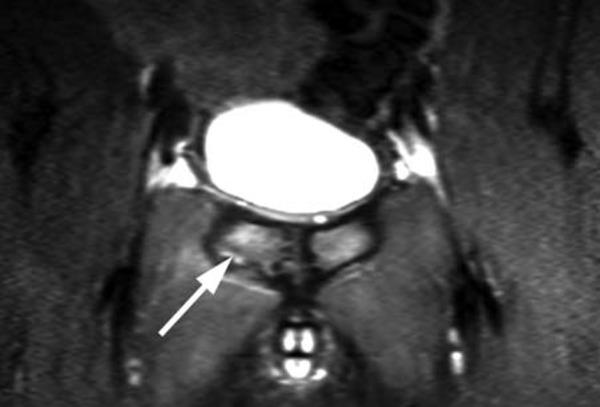

Orthopaedic magnetic resonance imaging challenge: apophyseal avulsions at the pelvis.

Apophyseal avulsion injuries of the hip and pelvis are frequent athletic injuries in children and adolescents, most commonly associated with explosive movement or sprinting. This article details typically encountered apophyseal injuries and their appearance on magnetic resonance imaging.